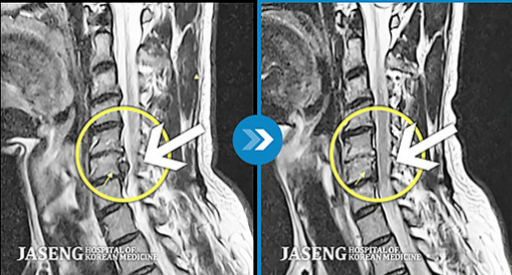

4. 노원 자생한방병원

위치: 노원역 1번 출구 인근

특징: 척추·관절 전문 한방 치료와 물리치료 병행.

평점: ★★★★★

노원자생한방병원: 한방 치료와 현대 물리치료를 병행, 허리 디스크 및 관절염에 효과적.